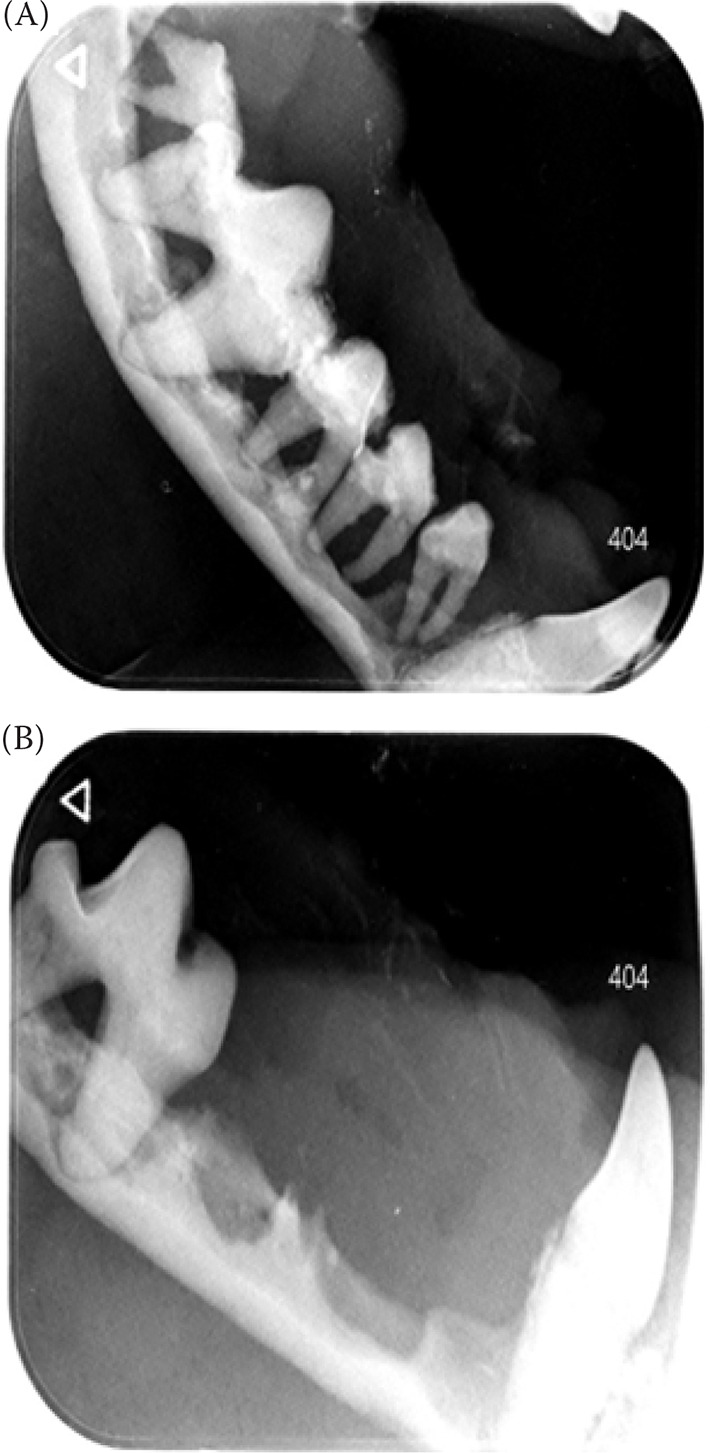

Abstract Image